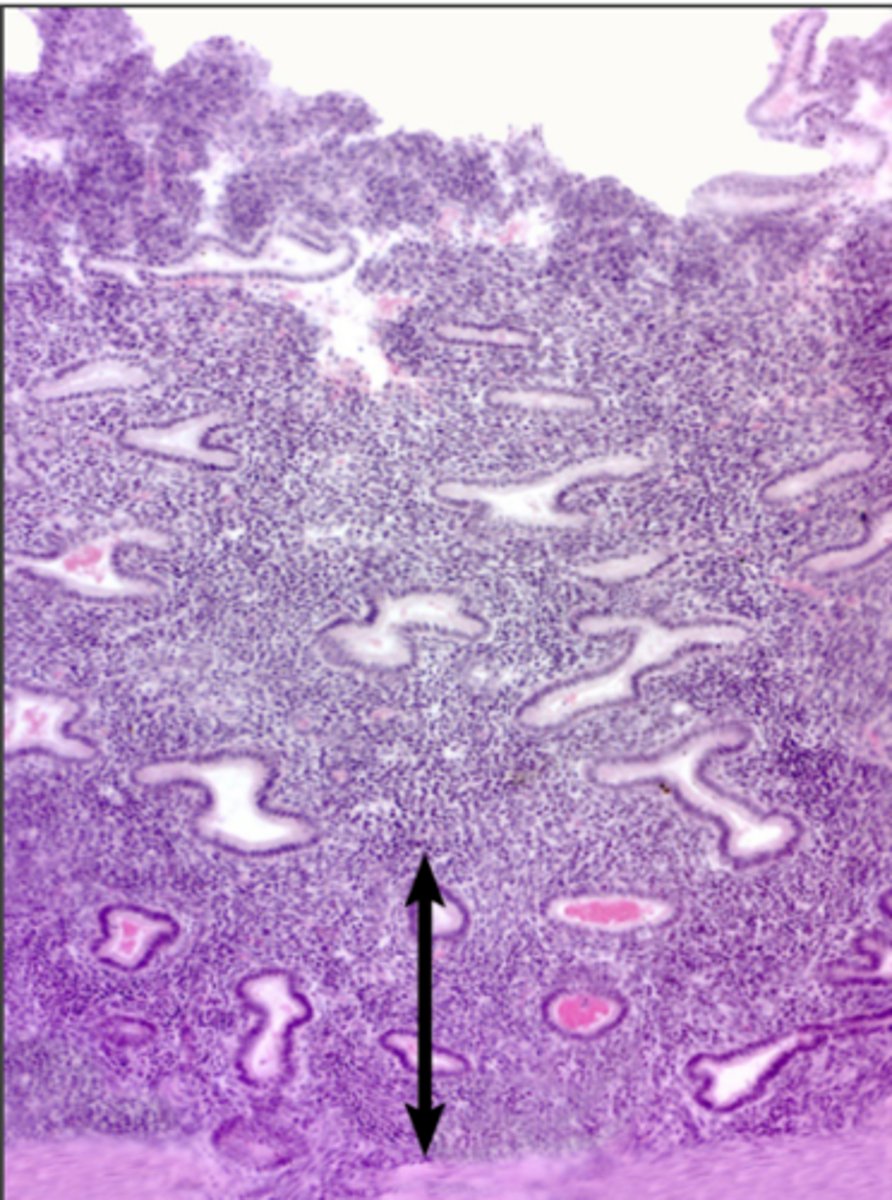

Endometrium

Endometrium

proliferate functional layer

secretory functional layer

menstrual functional layer

proliferate basal layer

secretory basal layer

menstrual basal layer

Uterine gland